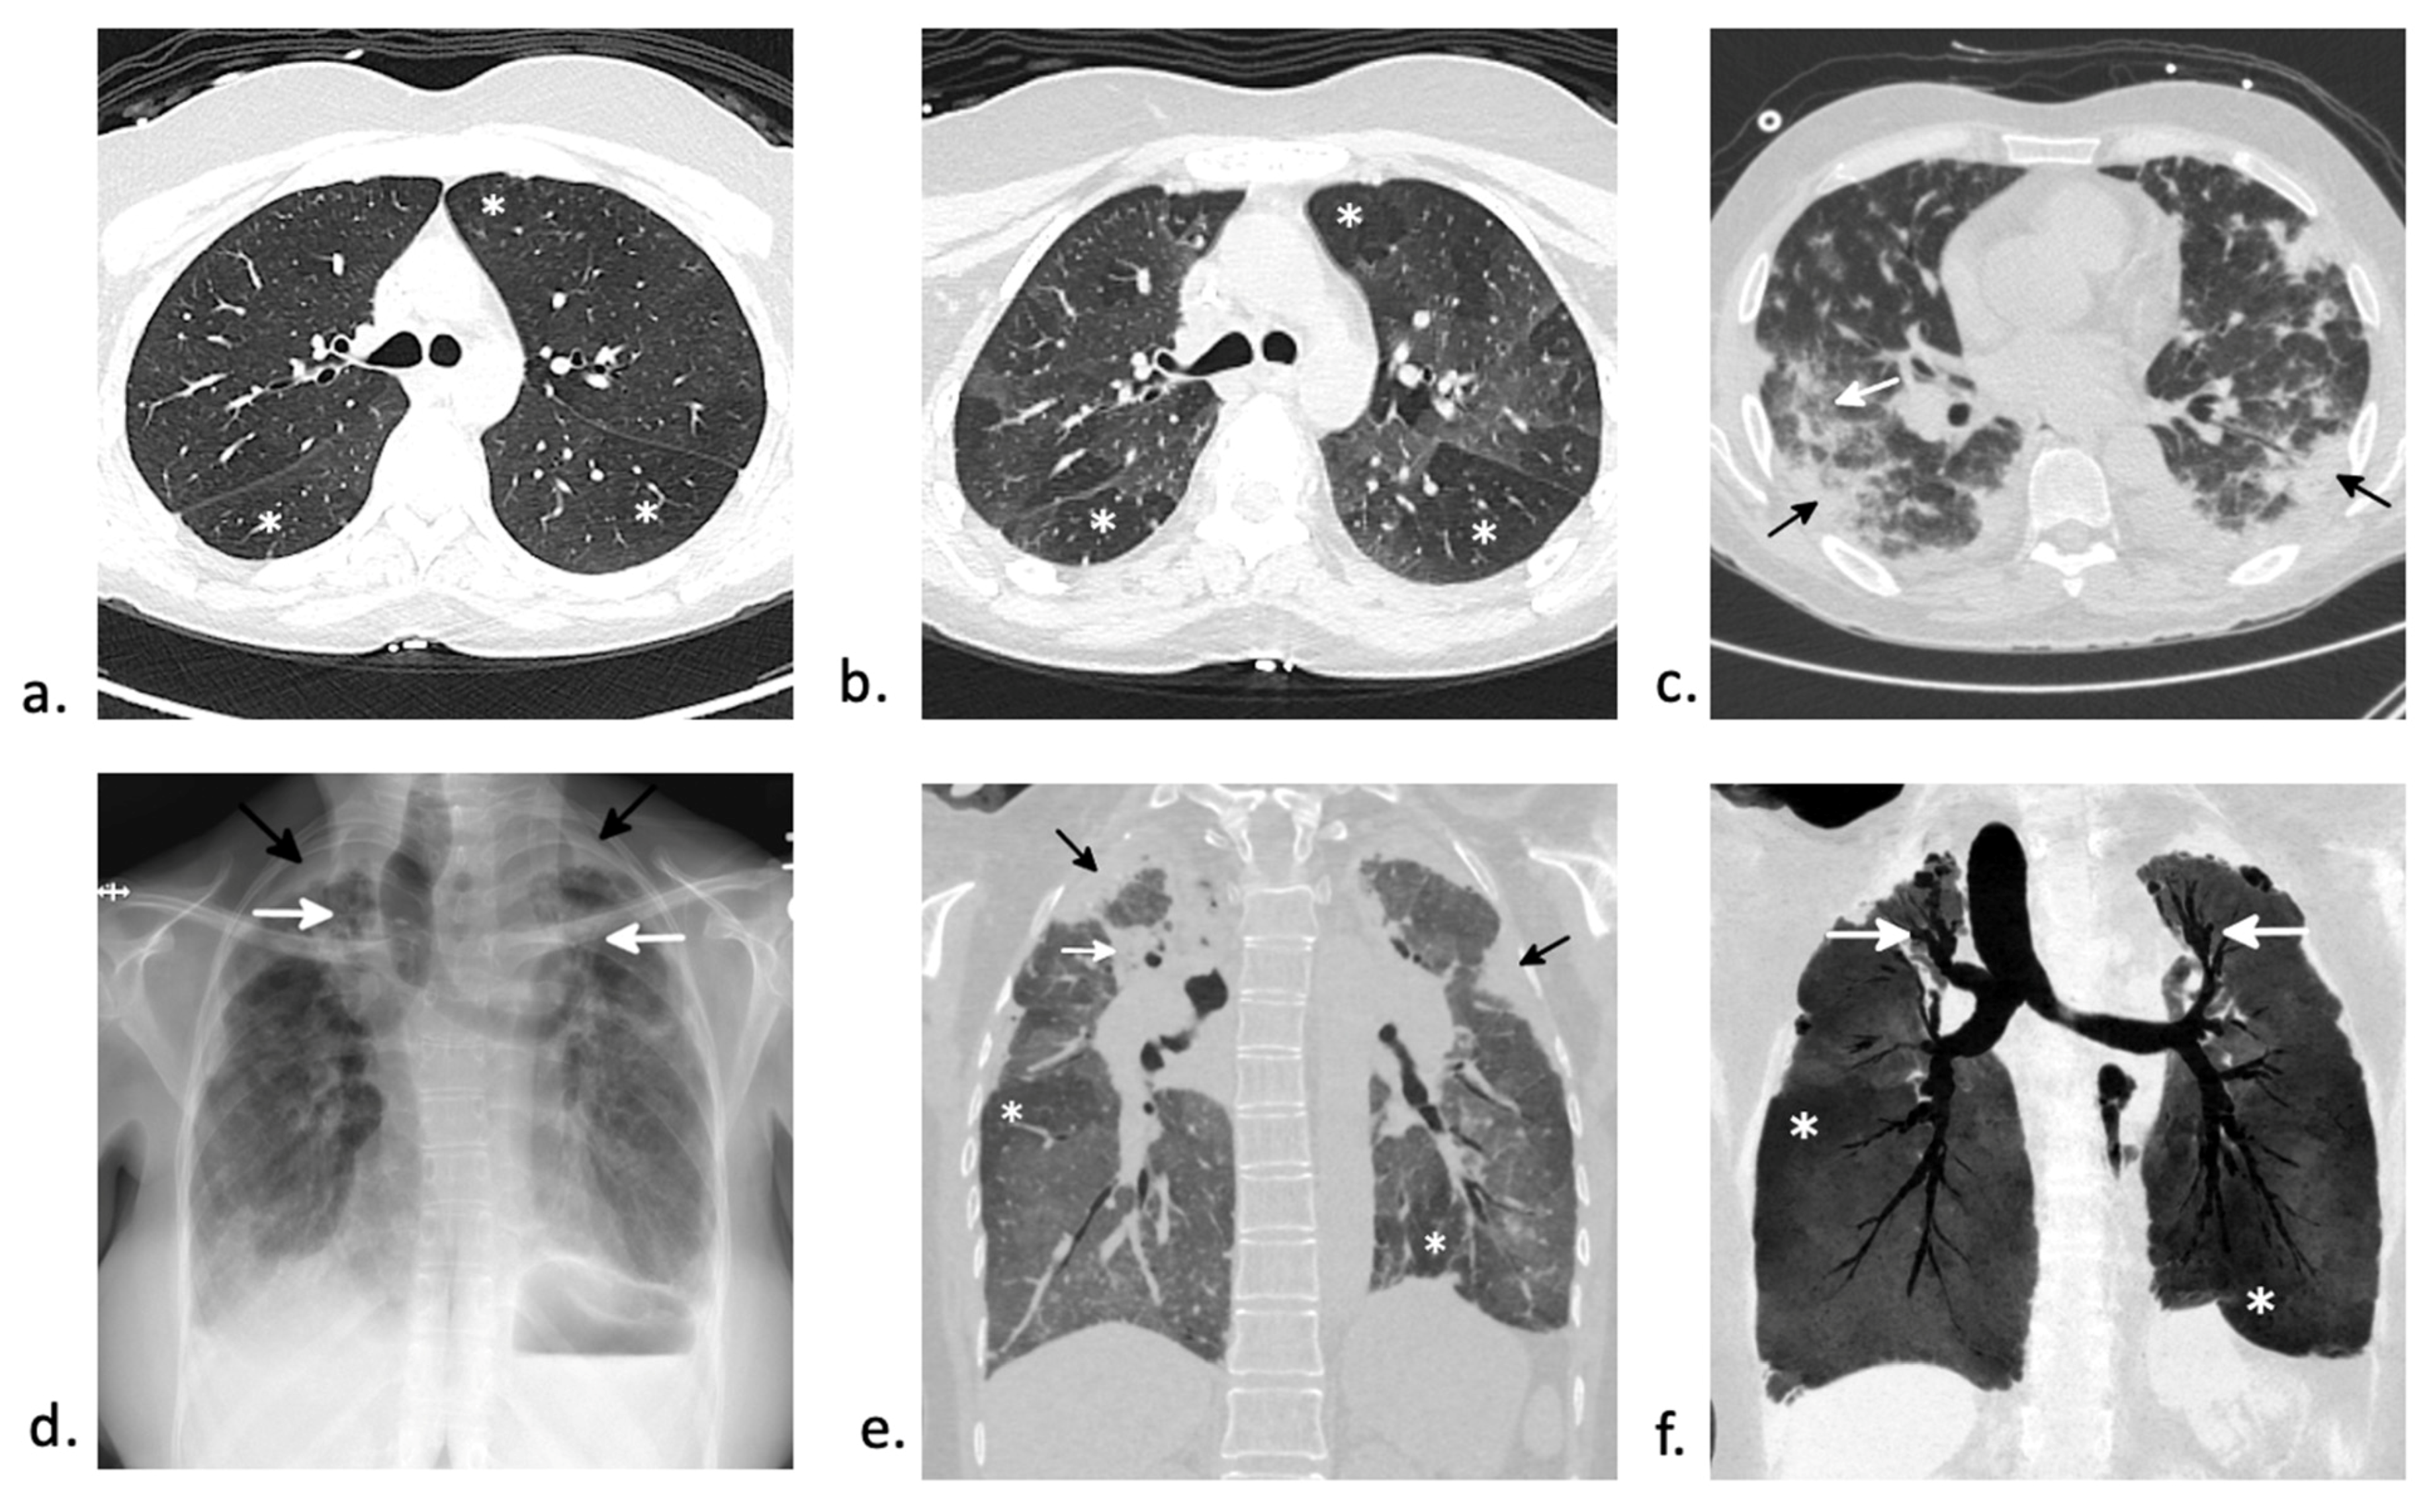

6.1. Bronchiolitis Obliterans Syndrome (BOS)

6.2. Organizing Pneumonia

6.4. Pulmonary Veno-Occlusive Disease (PVOD)